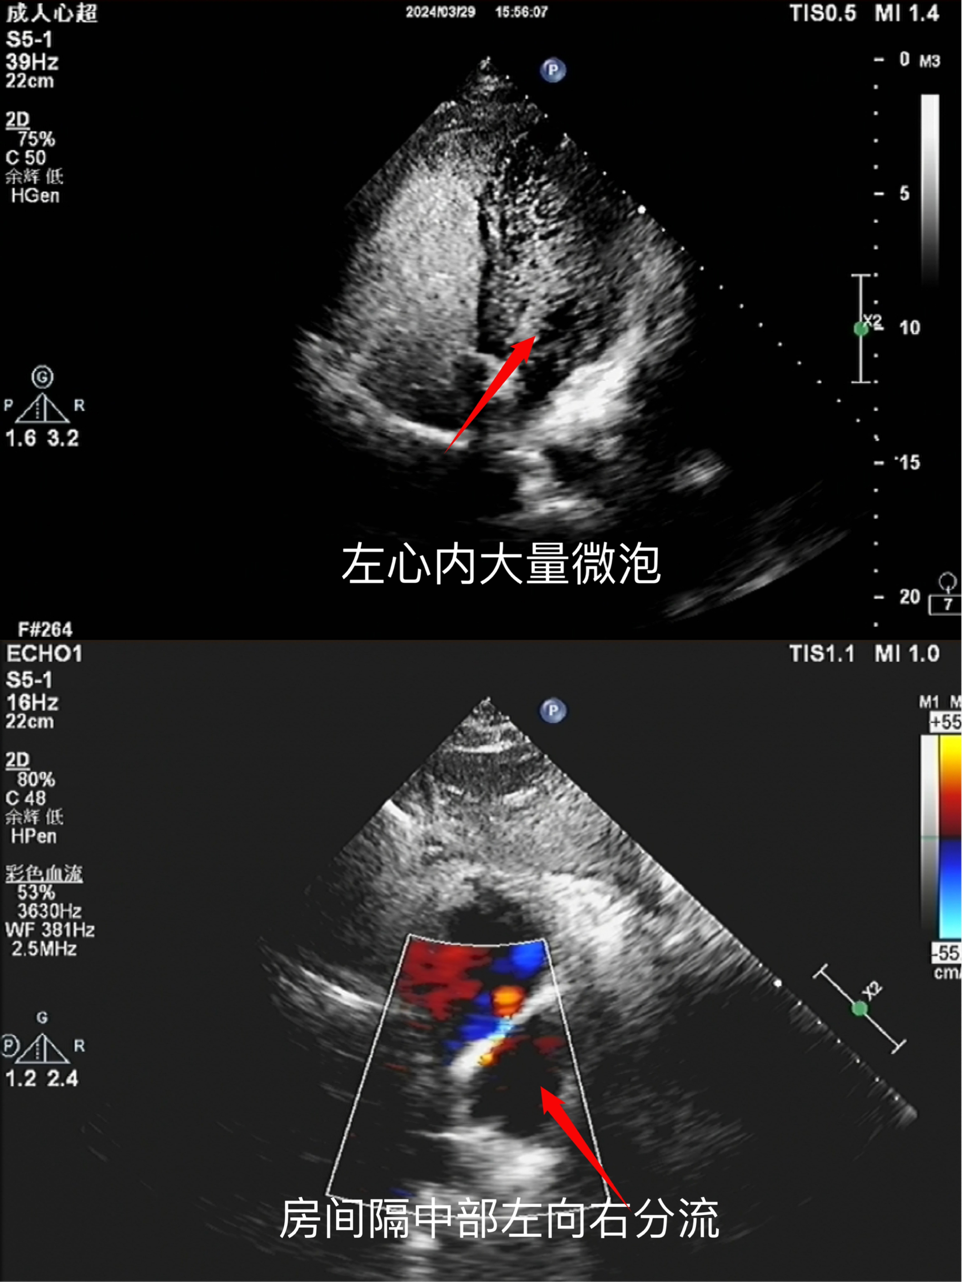

患者26歲,常于訓練后頭痛。近一年來,頭痛頻率、程度均增加,輾轉多家醫(yī)院,藥物治療后癥狀都未得到改善,此次來西部戰(zhàn)區(qū)總醫(yī)院治療,心臟超聲提示:卵圓孔未閉,右心聲學顯像提示造影后左心腔內微泡回聲。引起長期頭痛的原因,在這里找到了答案。

術前心臟彩超圖